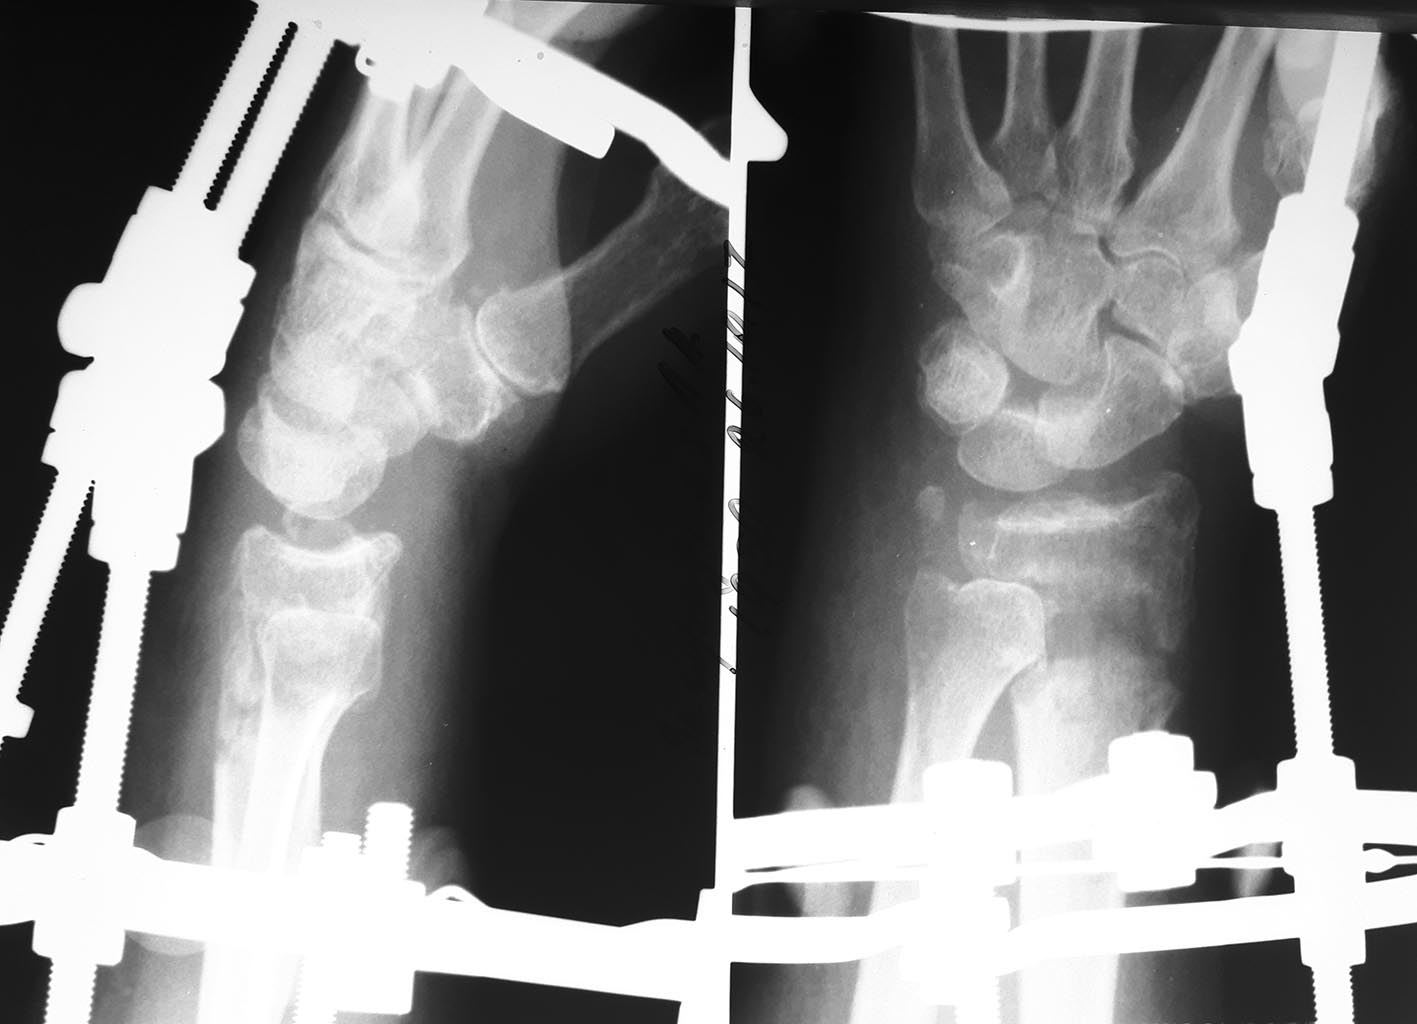

Пациентка 60 лет, 2 мес назад перелом дистального эпиметафиза лучевой кости, шиловидного отростка, Наложен АВФ.

По разным причинам продолжила лечение у хирурга, который проводил дистракцию. Сожалею, первичные снимки предоставить не могу. Рентген при поступлении и после "сброса" дистракции. Сейчас думаем, что с этим делать,четкого плана пока нет, какие у вас мысли по этому поводу?

срастись, наверное, не срослось, но и от компрессии, наверное, толку уже не будет, да и головка локтя в вывихе, тоже вряд ли на место через 2 мес встанет.

Как такового вывиха головки там нет, есть переудлинение лучевой кости, за счет которого нарушены взаимоотношения в DRUJ. Которые и могут улучшиться, если удастся уменьшить длину лучевой кости.